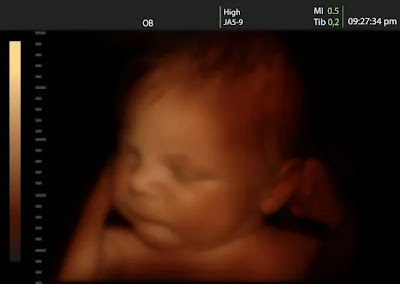

La ciencia ha descubierto que los bebés “practican” el llanto. De hecho, las investigaciones más recientes parecen confirmarlo. Un estudio de la Universidad de Durham ha observado que los bebés pueden hacer expresiones faciales en el segundo y tercer trimestre.

El estudio muestra cómo ciertas expresiones faciales relacionadas con el llanto y la risa son cada vez más comunes a medida que avanza el desarrollo fetal. Cuanto más avanza fisiológicamente el crecimiento de un bebé, más aumentan los movimientos faciales de lo que ellos llaman «gestalt de cara de llanto», desde el 0% a las 24 semanas hasta el 42% a las 35 semanas. Y durante el mismo período de tiempo, las expresiones faciales de «gestalt con cara de risa» aumentaron del 0 % al 35 %.

La autora de la investigación, Nadja Reissland, correlacionó estas observaciones con hitos del desarrollo fisiológico: si tales expresiones faltan parcial o totalmente, es una señal clara de que el desarrollo facial y general del niño no está en el rango normal.

¿Cómo pueden los científicos saber cuándo un feto está llorando usando ultrasonido 4D? No por el sonido del llanto o de las lágrimas, sino por ciertos movimientos y comportamientos enumerados en el estudio, comolevantar la ceja interna, bajar la ceja, arrugar la nariz, movimientos del labio inferior, etc.